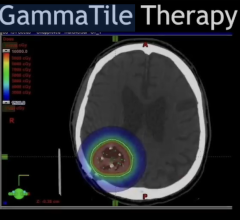

The campus will house large-scale facilities to produce positron emission tomography (PET) imaging agents. When injected into the body, these specialized radiopharmaceuticals, called biomarkers, detect and trace abnormal cellular functions that are associated with a variety of diseases. Visible using sophisticated imaging scanners, these biomarkers make it easier for physicians to non-invasively diagnose critical, life-threatening diseases in their earliest stages. They can also improve physicians’ ability to track the effectiveness of patient treatment plans.

State-of-the-art PET manufacturing facility: The center will house the latest technology in PET manufacturing, including dual cyclotrons, which can be used to produce large quantities of radioisotopes. It will also contain production facilities that allow for the simultaneous radiosynthesis of multiple imaging agents, for both commercial and research purposes.

Global PET Production Control Center: The center will also make it easier for pharmaceutical companies and academic institutions to monitor the production of their drugs at any of Cardinal Health’s PET manufacturing sites during multi-site clinical trials. The center’s PET production control center will provide video access to each of Cardinal Health’s PET manufacturing sites, effectively serving as a “mission control,” where partners can trouble shoot, offer technical assistance and more efficiently deploy resources against manufacturing challenges.